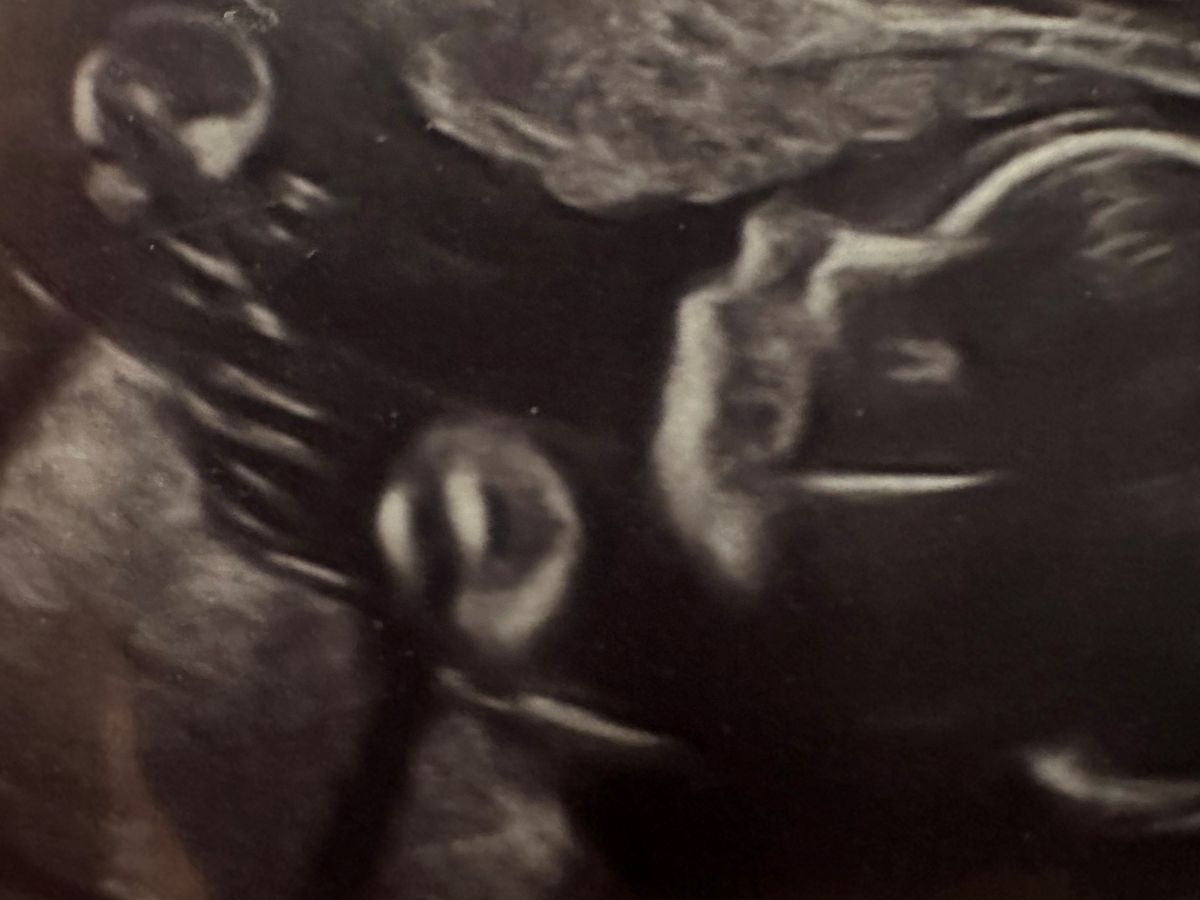

After five years, struggling with infertility, Emily and Evan Duffy finally conceived their “miracle baby:” Little Tyler. They celebrated with excitement and anticipation, but during the 20 week ultrasound, the doctor noticed the his heart was being pushed to the right side of his chest. After undergoing a fetal echocardiogram, MRI and multiple ultrasounds, Little Tyler was diagnosed with a Congenital Diaphragmatic Hernia (CDH).